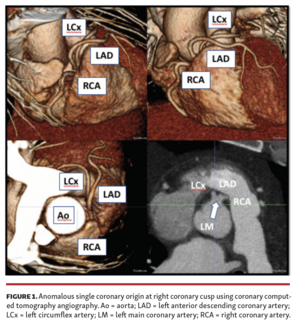

Vladimir Lakhter, DO; Kiersten Frenchu, MD; David Lakhter, BS; Pravin Patil, MD

This case of a rare single coronary artery demonstrates that cardiac CTA is an essential tool to define artery course and provide further risk stratification.